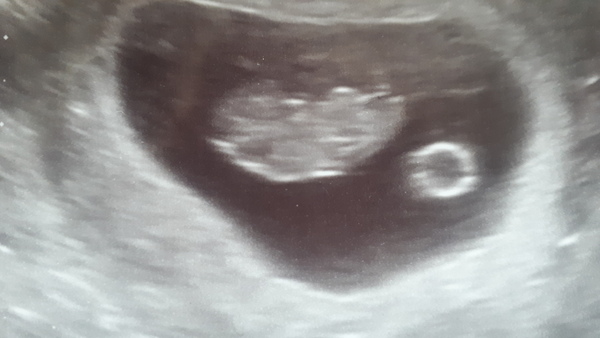

Hello. Looking for advice or anyone with a similar scan. My 9 week reassurance scan shows a dark spot at what appears to be behind the baby's head.

I am a bit concerned that there is a lot of fluid in the baby's neck. Don't have my 12 week scan for a few weeks yet.

Midwife sonographer here. That 9 week scan looks absolutely fine. Congratulations x